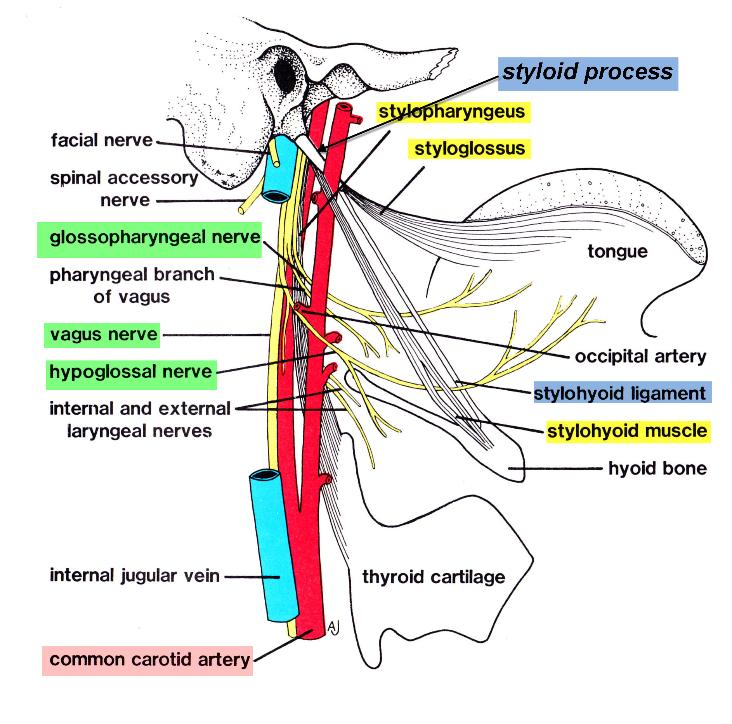

Common carotid

- carotid sheath

- 頸部無分支

External carotid

- lingual a.

- hyoglossus m. 深層,digastric下

Superior thyroid artery

- Infrahyoid br.

- Sup. laryngeal a.

- SCM br.

- Cricothryoid br.

Internal carotid a.

- 進入carotid canal 前無分支

- CN X 伴行

- Carotid canal入顱

- carotid a. 夾 Stylopharyngeus m.(CN IX) , Styloglossus m. (CN XII)

分隔ECA,ICA